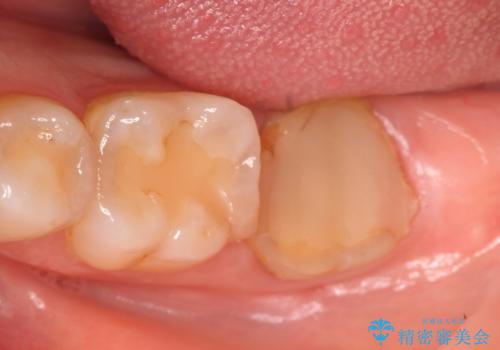

- 左下の一番奥の歯が時折激しく痛むので診て欲しいといらっしゃった方の症例です。以前に他院を受診したところ、そもそも被せ物を入れるスペースがないため抜歯しかないと言われたとのことでした。

診査の結果根尖病変を認めたため再根管治療を行った後に、被せ物を入れるスペースを作るため歯冠延長術を行いました。